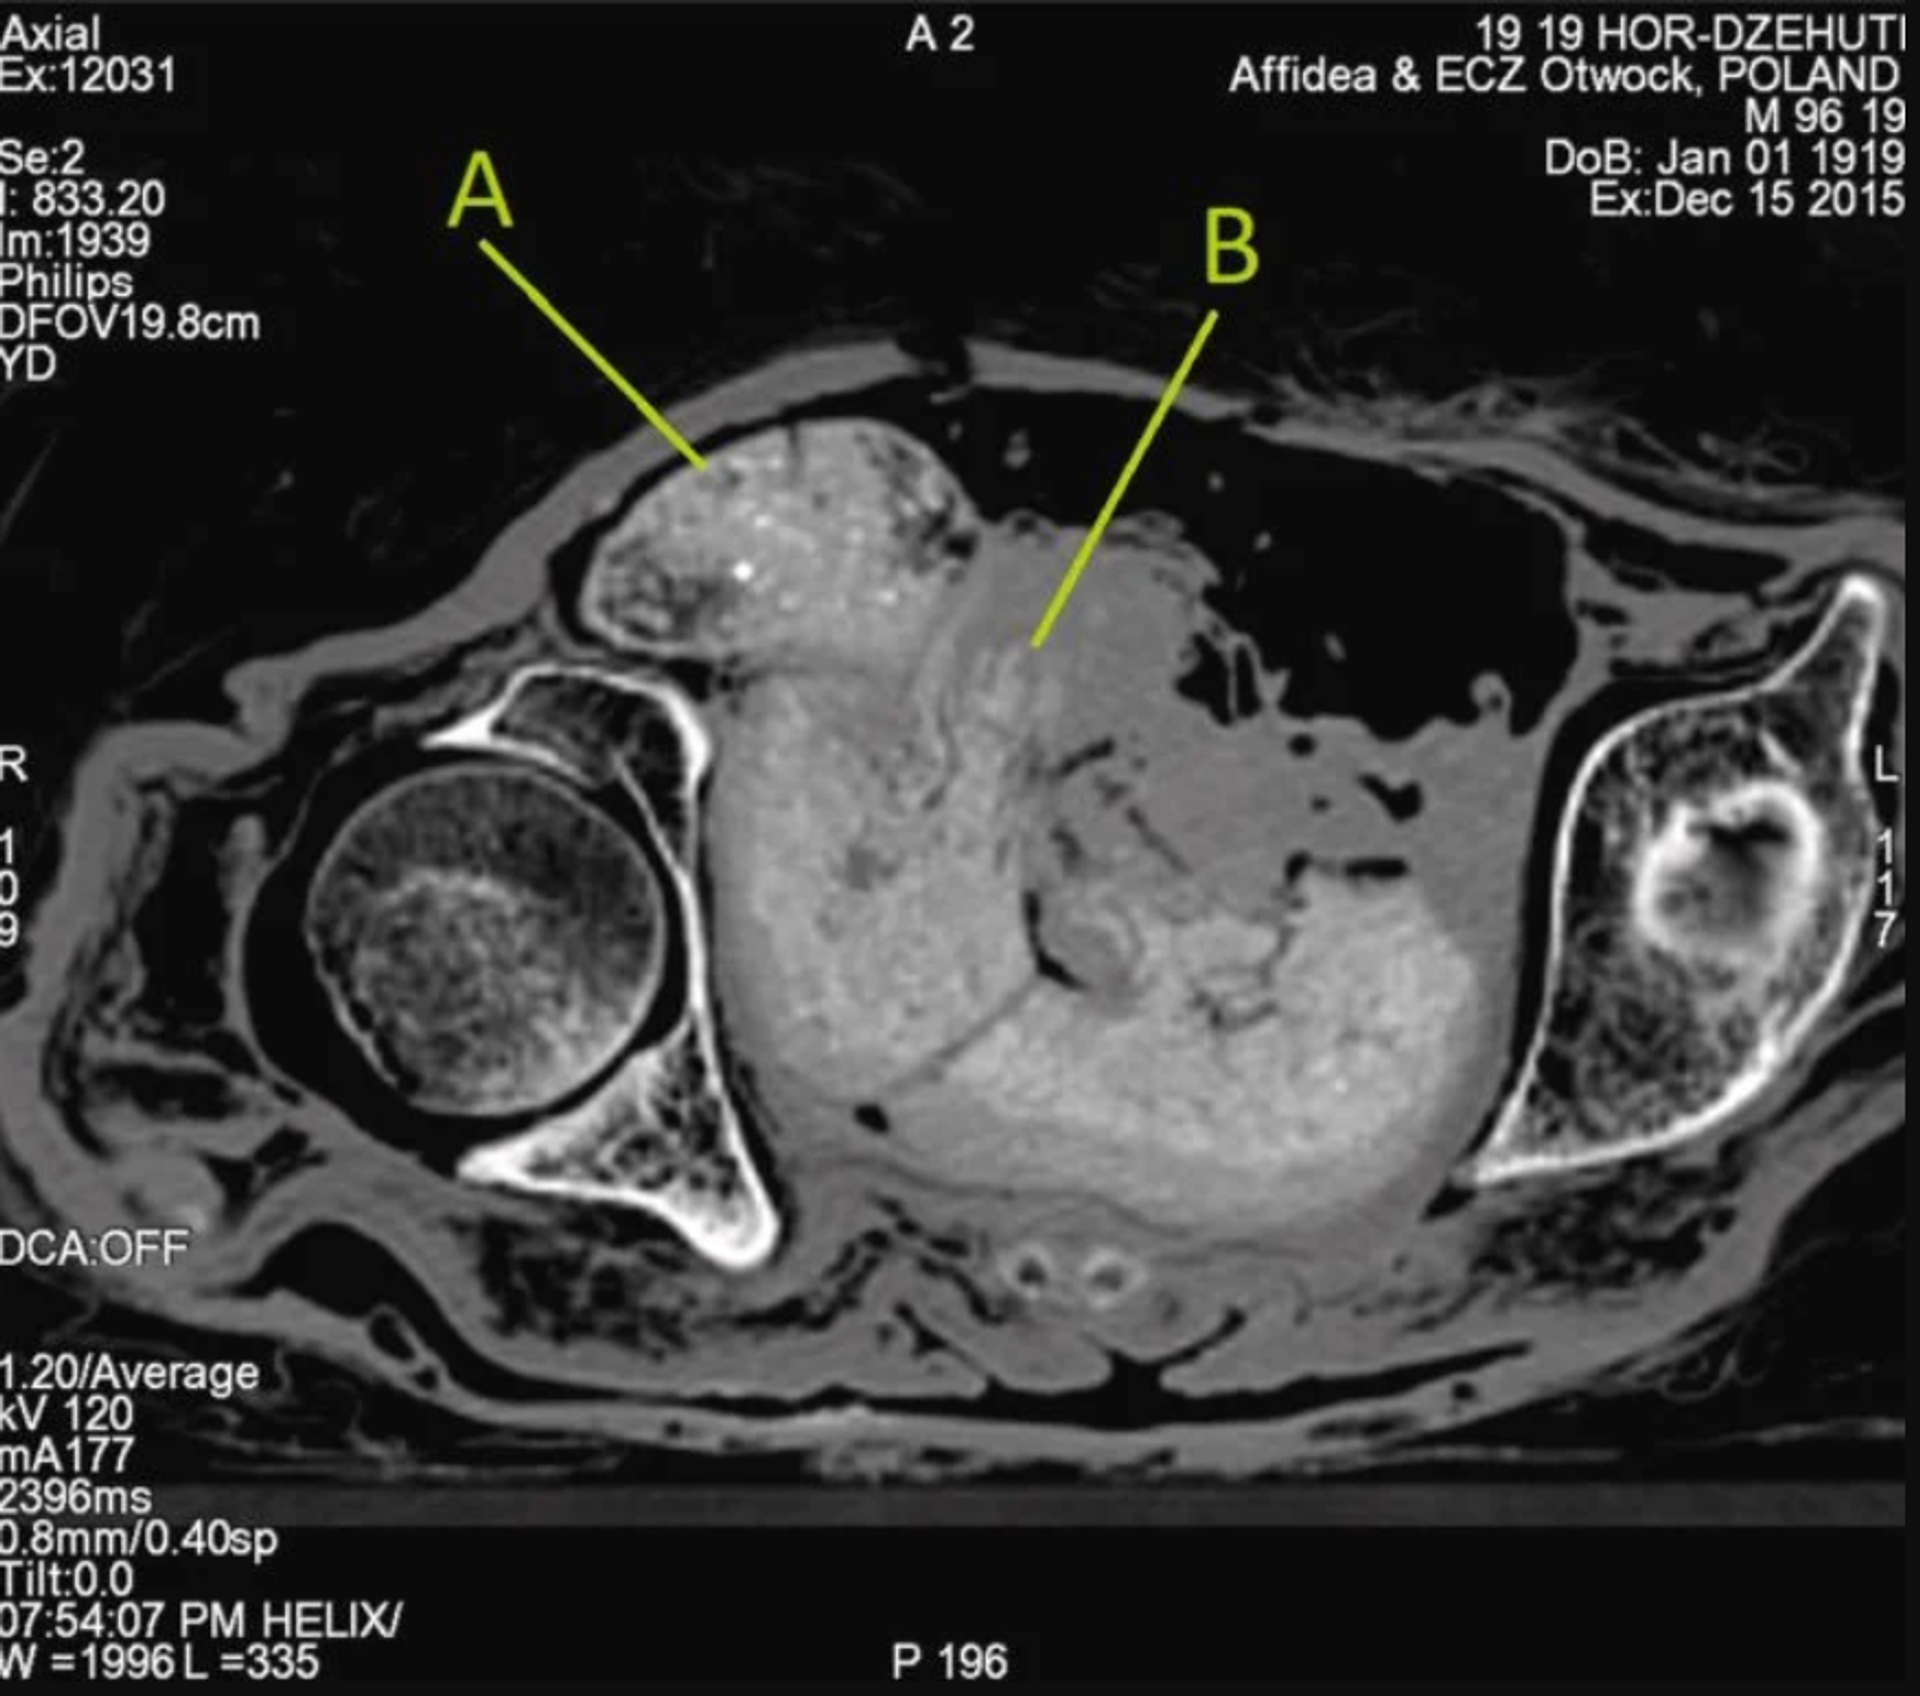

Además, los minerales lixiviados de los huesos del feto se habrían depositado en los tejidos blandos del propio feto y del útero que lo rodea, lo que daría lugar a un contenido mineral superior al esperado. Esto significa que estos tejidos tendrían una mayor radiodensidad en las tomografías.

El análisis del equipo también determinó que, debido a la posición del feto y al estado cerrado del canal de parto, la mujer no murió en el parto. Los análisis anteriores determinaron que la Dama Misteriosa tenía entre 20 y 30 años cuando murió y que su embarazo tenía entre 26 y 30 semanas.